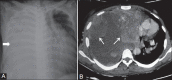

Tumors of the pleura are not uncommon and diagnosis is clinched by combined imaging and clinical correlation. Malignant tumors are more common than benign tumors. Initial imaging modalities are chest radiography and Computed Tomography (CT). Further characterization may be required using Ultrasoundgraphy (USG), Magnetic resonance Imaging (MRI) and PET-CT. Biopsy remains gold standard. This article highlights various common and uncommon tumors of pleura and characteristic imaging findings.